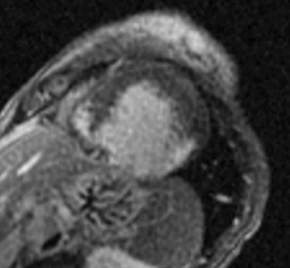

Fig.: 6., 7., 8.: MRI: Extended myocardial infarct of the inferior ventricular wall Late phase contrast enhancement in the thin inferior wall of the ventricle in cross sectional and longitudinal images, MRI